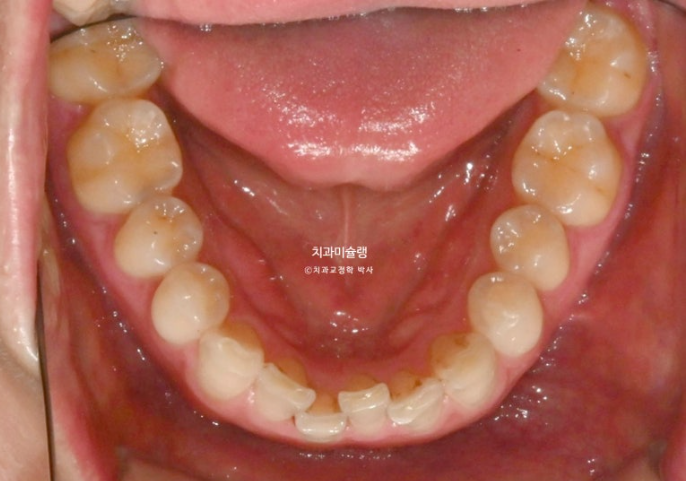

앞니 높낮이가 맞아지면 들쑥날쑥 했던 잇몸라인은 자연스럽게 맞아집니다.

앞니만 교정하는 부분교정이기에 어금니 교합은 그대로 유지됩니다.

이제 전후 비교 보겠습니다.

총 치료기간은 6개월 입니다.

25.04~25.10

중심선 불일치는 부분교정의 한계점으로 그대로 덧니를 포함한 배열만은 완벽합니다.

특히 아래 앞니 중 튀어나와있던 파란 화살표 앞니는 배열 과정에서 잇몸라인도 자연스럽게 주변과 맞아집니다.